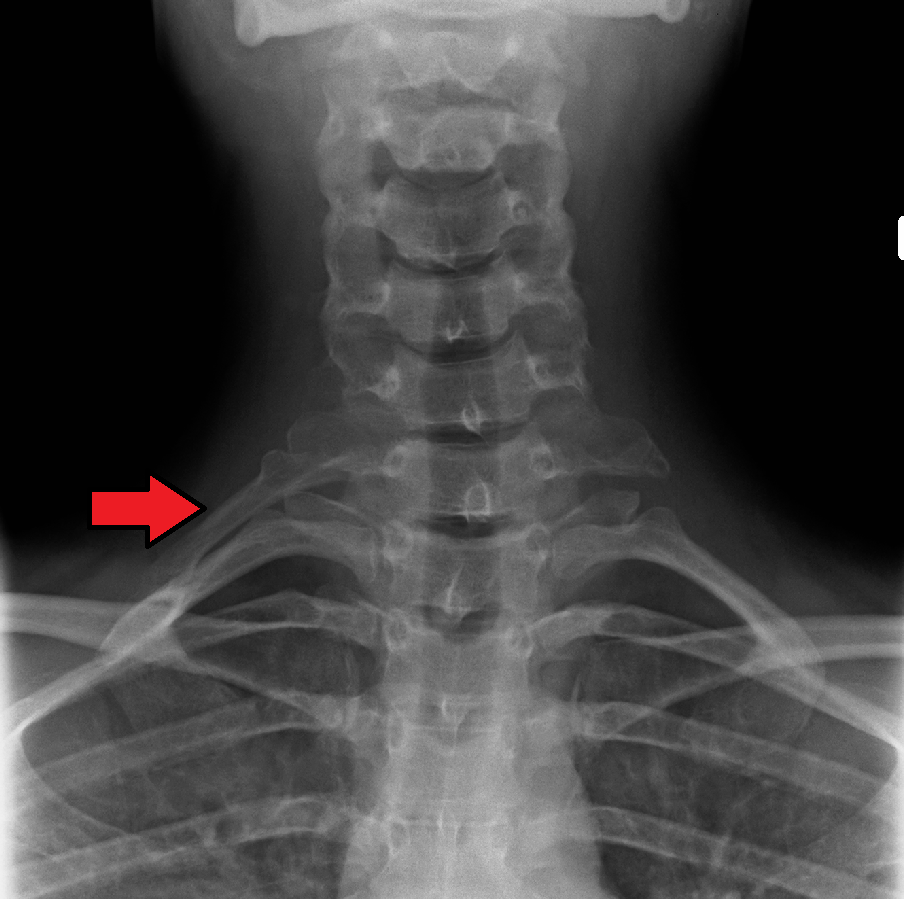

- '''첫 번째 갈비뼈''': 가장 위쪽에 있으며, 가장 짧고 넓고 납작하며 가장 많이 휘어 있다. 위아래 면과 안팎 가장자리가 뚜렷하다.

- 머리는 작고 둥글며, 첫 번째 흉추 몸통과 연결되는 관절면이 하나만 있다.

- 목은 좁고 둥글다.

- 결절은 두껍고 바깥쪽 가장자리에 있으며, T1 척추의 가로 돌기와 연결된다.

- 각은 없지만 결절 부위에서 약간 위로 볼록하게 휘어진다.

- 몸통 윗면에는 두 개의 얕은 홈이 있다. 앞쪽 홈으로는 쇄골하 정맥이, 뒤쪽 홈으로는 쇄골하 동맥과 상완 신경총의 아래쪽 줄기가 지나간다. 두 홈 사이에는 사각근 결절이라는 작은 융기가 있어 앞 사각근이 부착된다. 뒤쪽 홈 뒤에는 중간 사각근이 부착되는 거친 부위가 있다.